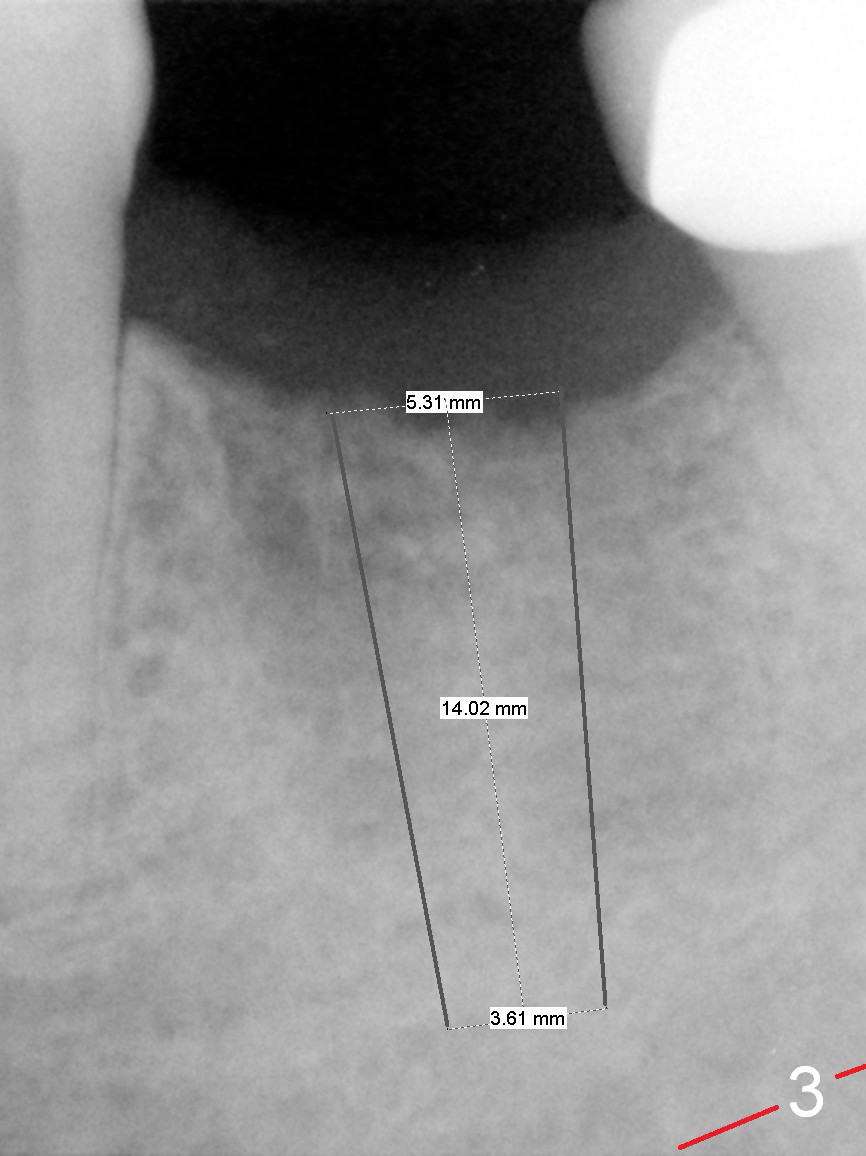

A 68-year-old man had the tooth #19 extracted more than 6 months ago (Fig.1). When his wife has had an immediate implant placed, he decides to have his implant placed. After incision, use the 5 mm implant positioner to check the width of the crestal bone. If it is less than 6 mm, the implant length will be most likely 14 mm. Clinical exam has revealed moderate ridge atrophy. Anyway, the initial osteotomy is 12 mm. It should pass the apices of the mesial (M) and distal (D) sockets (Fig.2 ^) in the middle of the septum (as compared to Fig.1 S). If there is enough safety margin, the osteotomy depth will be set at 14 mm (Fig.3 (red dashed line: the superior border of the Inferior Alveolar Canal)). There is no indication for intraop localized use of antibiotic.